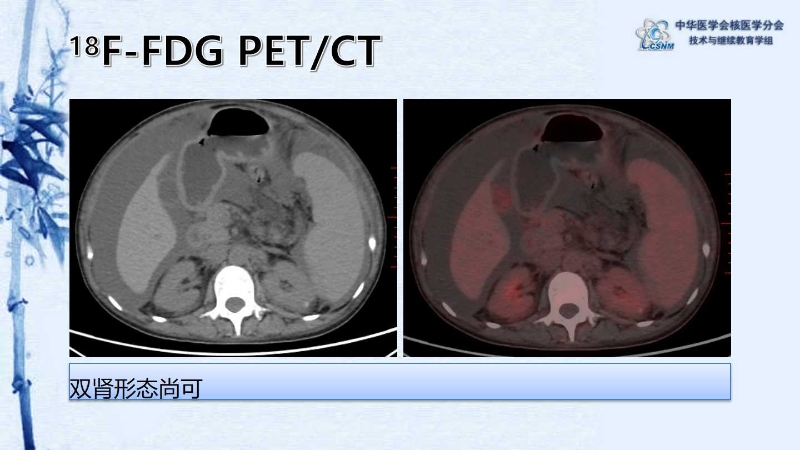

【CSNM继教学组】病例E54-赵红光:以TAFRO综合征起病的Castleman 病